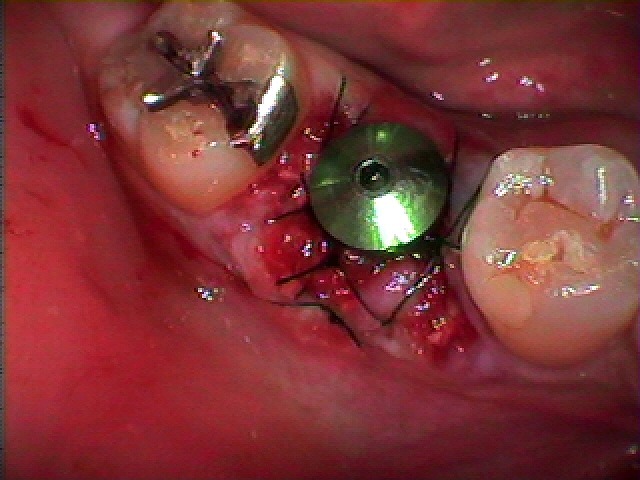

縫合して終了となります